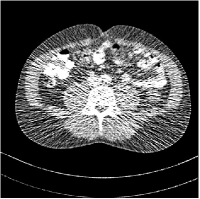

We conduct experiments on three slices (L067-slice100, L192-slice100, L506-slice100) of the Mayo Clinic data. Fig. 2 shows the reconstruction of L067-slice100 using FBP, PWLS-EP, PWLS-ST, PWLS-MRST2, PWLS-MRST3, PWLS-MRST5, and PWLS-MRST7, respectively at incident photon intensity . TABLE I lists the RMSE, PSNR, and SSIM values of reconstructions of the three test slices, with the best values bolded. The two-layer model (MRST2) provides the best RMSE and PSNR values among the methods. However, when we consider the SSIM criterion, MRST5 and MRST7 outperform ST and MRST2. So which MRST model is better? By observing the reconstructed images, we see that although MRST2 and ST have lower RMSE and higher PSNR values than MRST5 and MRST7, they sacrifice some sharpness of the central region and suffer from loss of details. The deeper models have a more positive effect in maintaining subtle features, which is clearly more essential to clinic medical diagnosis. Furthermore, after considerable parameter tuning, we have observed that the deeper models offer more stable image quality as is varied, i.e., they are more robust to oversmoothing.